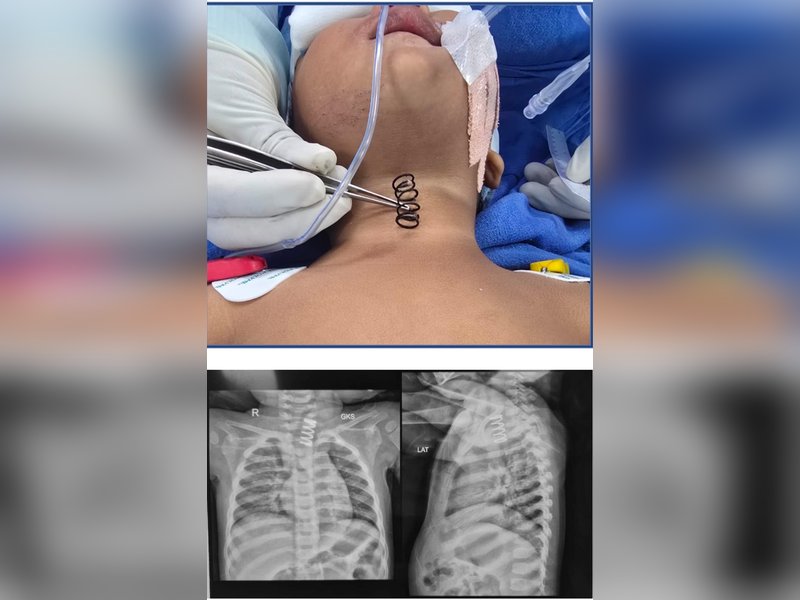

"Pankaj, his friend was just 5 metres away, but he didn't tell me anything. When we touched his head, then we saw there was an injury on Shivam's head. Then the doctor called us to do a CT scan of his skull."

"When we were taking him for the CT scan, then my brother came and said that he had got a call from SI Suresh Chandra who informed me that Shivam has been beaten with helmets. The lady technician informed me that there is a major injury to his head.

"Later, Shivam was slowly recovering from his injuries. But on January 11, doctors said that there was an infection in the brain and they had installed a pipe in his spine and head, but it didn't go well. On January 19, around 1 pm, he died," he told IANS.